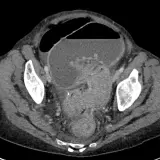

Over 2,100 interactive radiology cases, curated by radiologists for your level of training. Scroll, window, and view cases full screen — just like on PACS. Click linked findings in each writeup to jump straight to them on the image. Cases include sample reports, a focused discussion section, original illustrations, and videos.

Des cas entièrement interactifs avec les outils attendus d'un PACS — défilement, fenêtrage, zoom, déplacement, mesures, ROI et mode plein écran.

Des annotations détaillées mettent en évidence les résultats clés directement sur les cas. Cliquez sur les résultats liés dans les descriptions de cas pour accéder à leur emplacement exact sur l'examen.